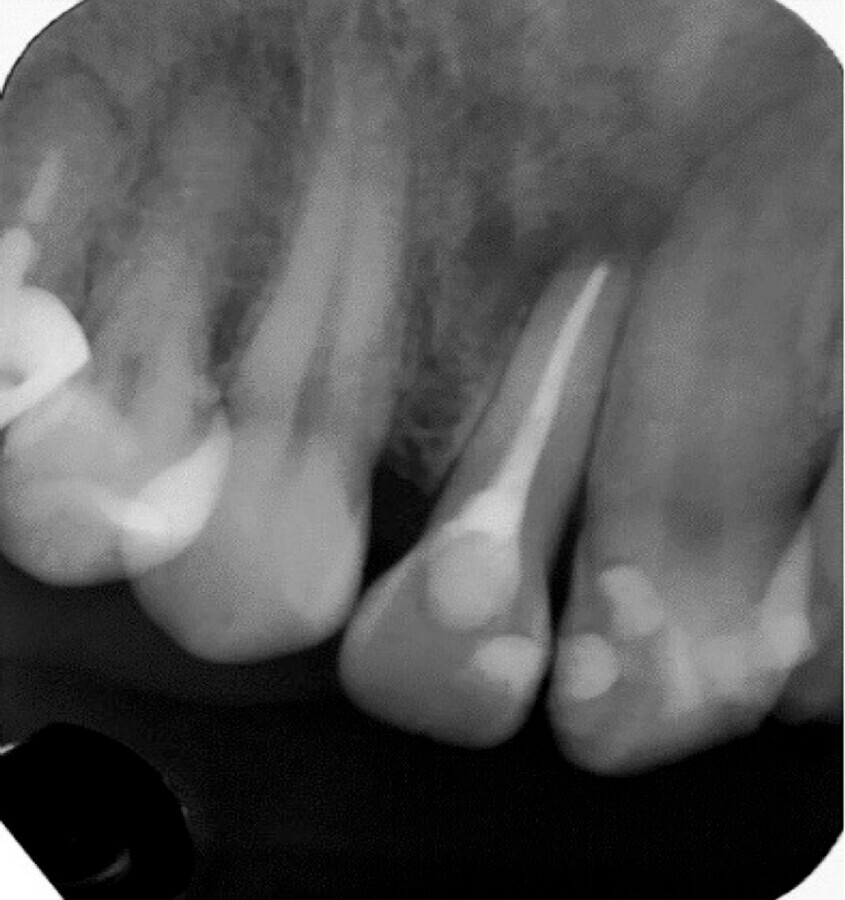

Figura 1. Fotografías iniciales del caso (A, B y C). Medición y registro de recesiones y lesiones LCNCs con sondeo (D, E y F). Evaluación de la lesión periapical en el diente 22 con superposición de aspecto tomográfico vestibular (E).

La literatura menciona tres métodos para evaluar el grosor del fenotipo gingival de un diente defectuoso: la transparencia de la sonda dentro del surco gingival es el método más utilizado hoy en día, puesto que ha demostrado ser sencillo y eficaz para evaluar el espesor gingival5,6. Las recesiones fueron clasificadas según Miller y las LCNCs según la clasificación de Cairo7. En la interpretación radiográfica dentoalveolar del diente 22, se observó una zona radiolúcida difusa, circundante no definida, con material radiopaco extralimitando el ápice, determinando una periodontitis apical, derivada de tratamiento endodóntico deficiente, que requirió respaldo tomográfico. La paciente cooperó en todo momento y estuvo atenta para resolver este grupo de problemas que la aquejaba, señalando la preocupación por atenderlos de inmediato con expectativa positiva (Figura 1).